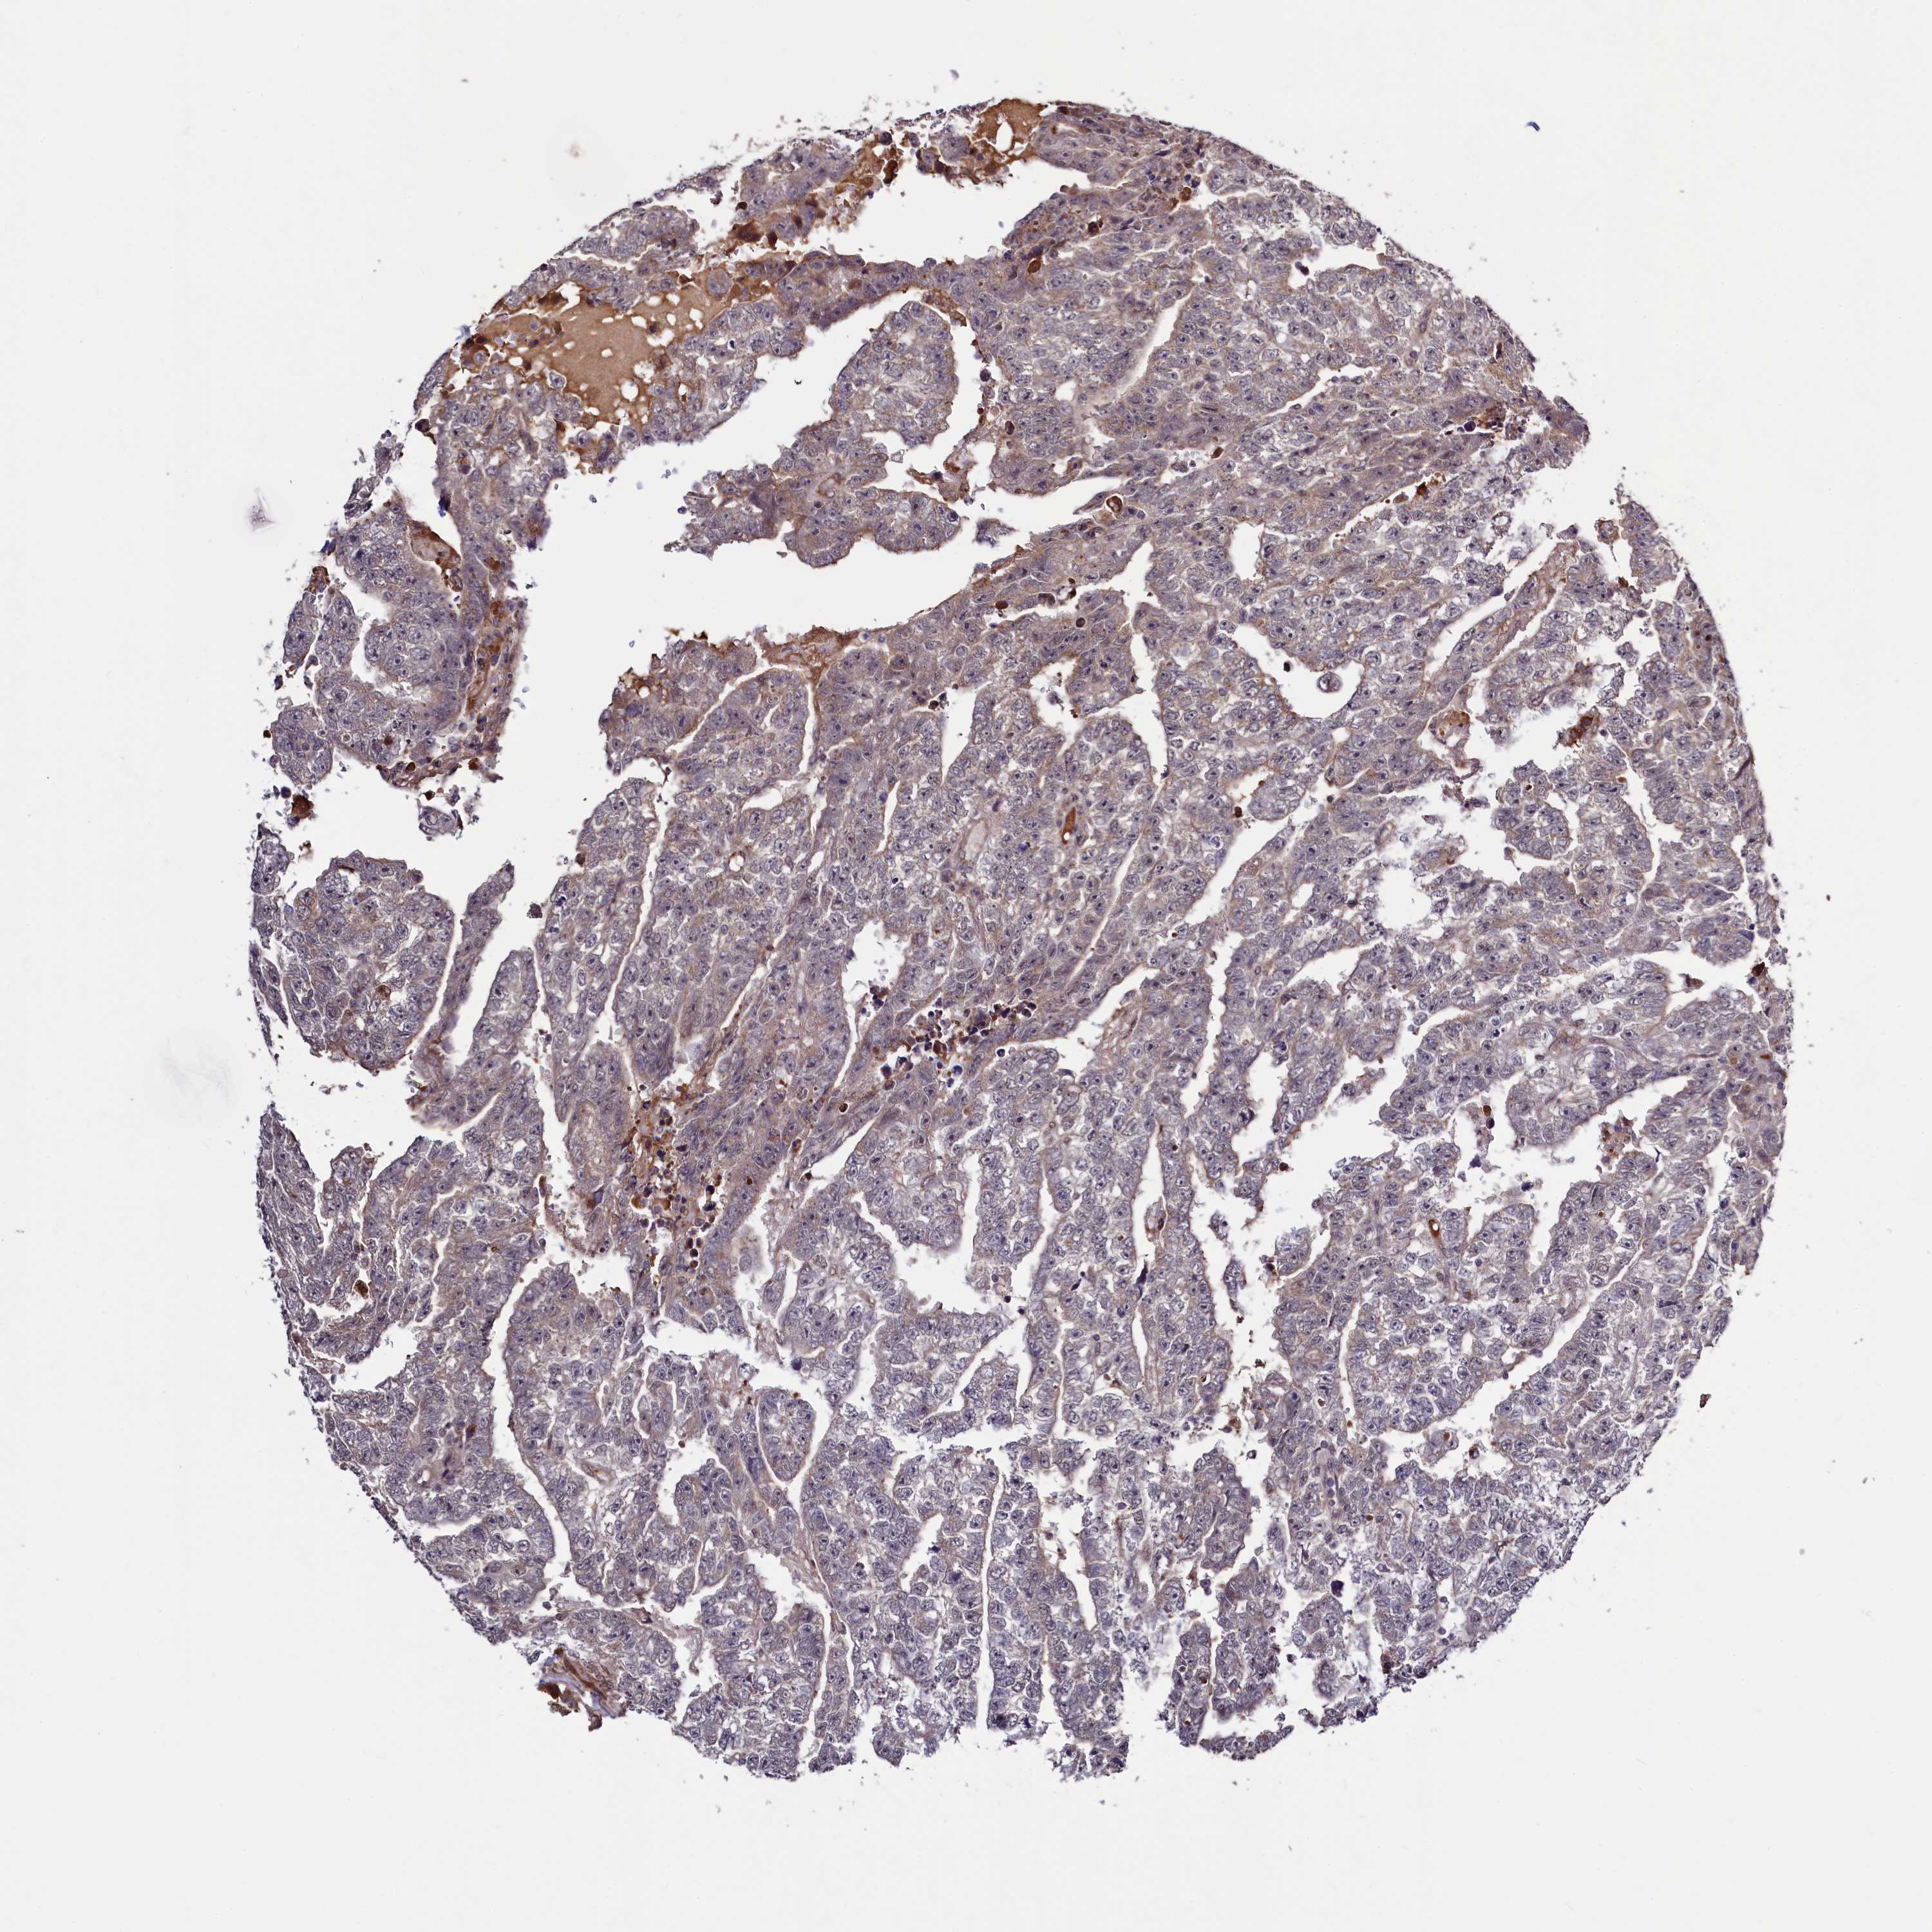

TESTIS CANCER - Protein expressioni

A mouse-over function shows sample information and annotation data. Click on an image to view it in a full screen mode. Samples can be filtered based on level of antibody staining by selecting one or several of the following categories: high, medium, low and not detected. The assay and annotation is described here.

Note that samples used for immunohistochemistry by the Human Protein Atlas do not correspond to samples in the TCGA dataset.

Antibody stainingi

Antibody staining in the annotated cell types in the current human tissue is reported as not detected, low, medium, or high, based on conventional immunohistochemistry profiling in selected tissues. This score is based on the combination of the staining intensity and fraction of stained cells.

Each image is clickable and will lead to virtual microscopy that enables deeper exploration of all samples and also displays staining intensity scores, fraction scores and subcellular localization as well as patient and tissue information for each sample.

Antibody HPA040196

Antibody HPA040213

Carcinoma, Embryonal, NOS

Seminoma, NOS